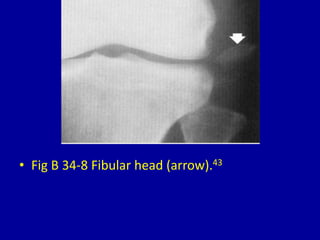

This document provides descriptions and images of avulsion injuries at various anatomical locations in the body. Avulsion injuries refer to the tearing away of a tendon, ligament, or muscle from the bone. The document lists 17 figures showing examples of avulsion injuries at locations such as the ischial tuberosity, anterior superior iliac spine, anterior inferior iliac spine, symphysis pubis, lesser trochanter, greater trochanter, fibular head, tibial eminence, posterior cruciate ligament, tibial tuberosity, inferior pole of the patella, calcaneal tuberosity, anterior and posterior capsule of the ankle joint, greater and lesser tuberosity of the